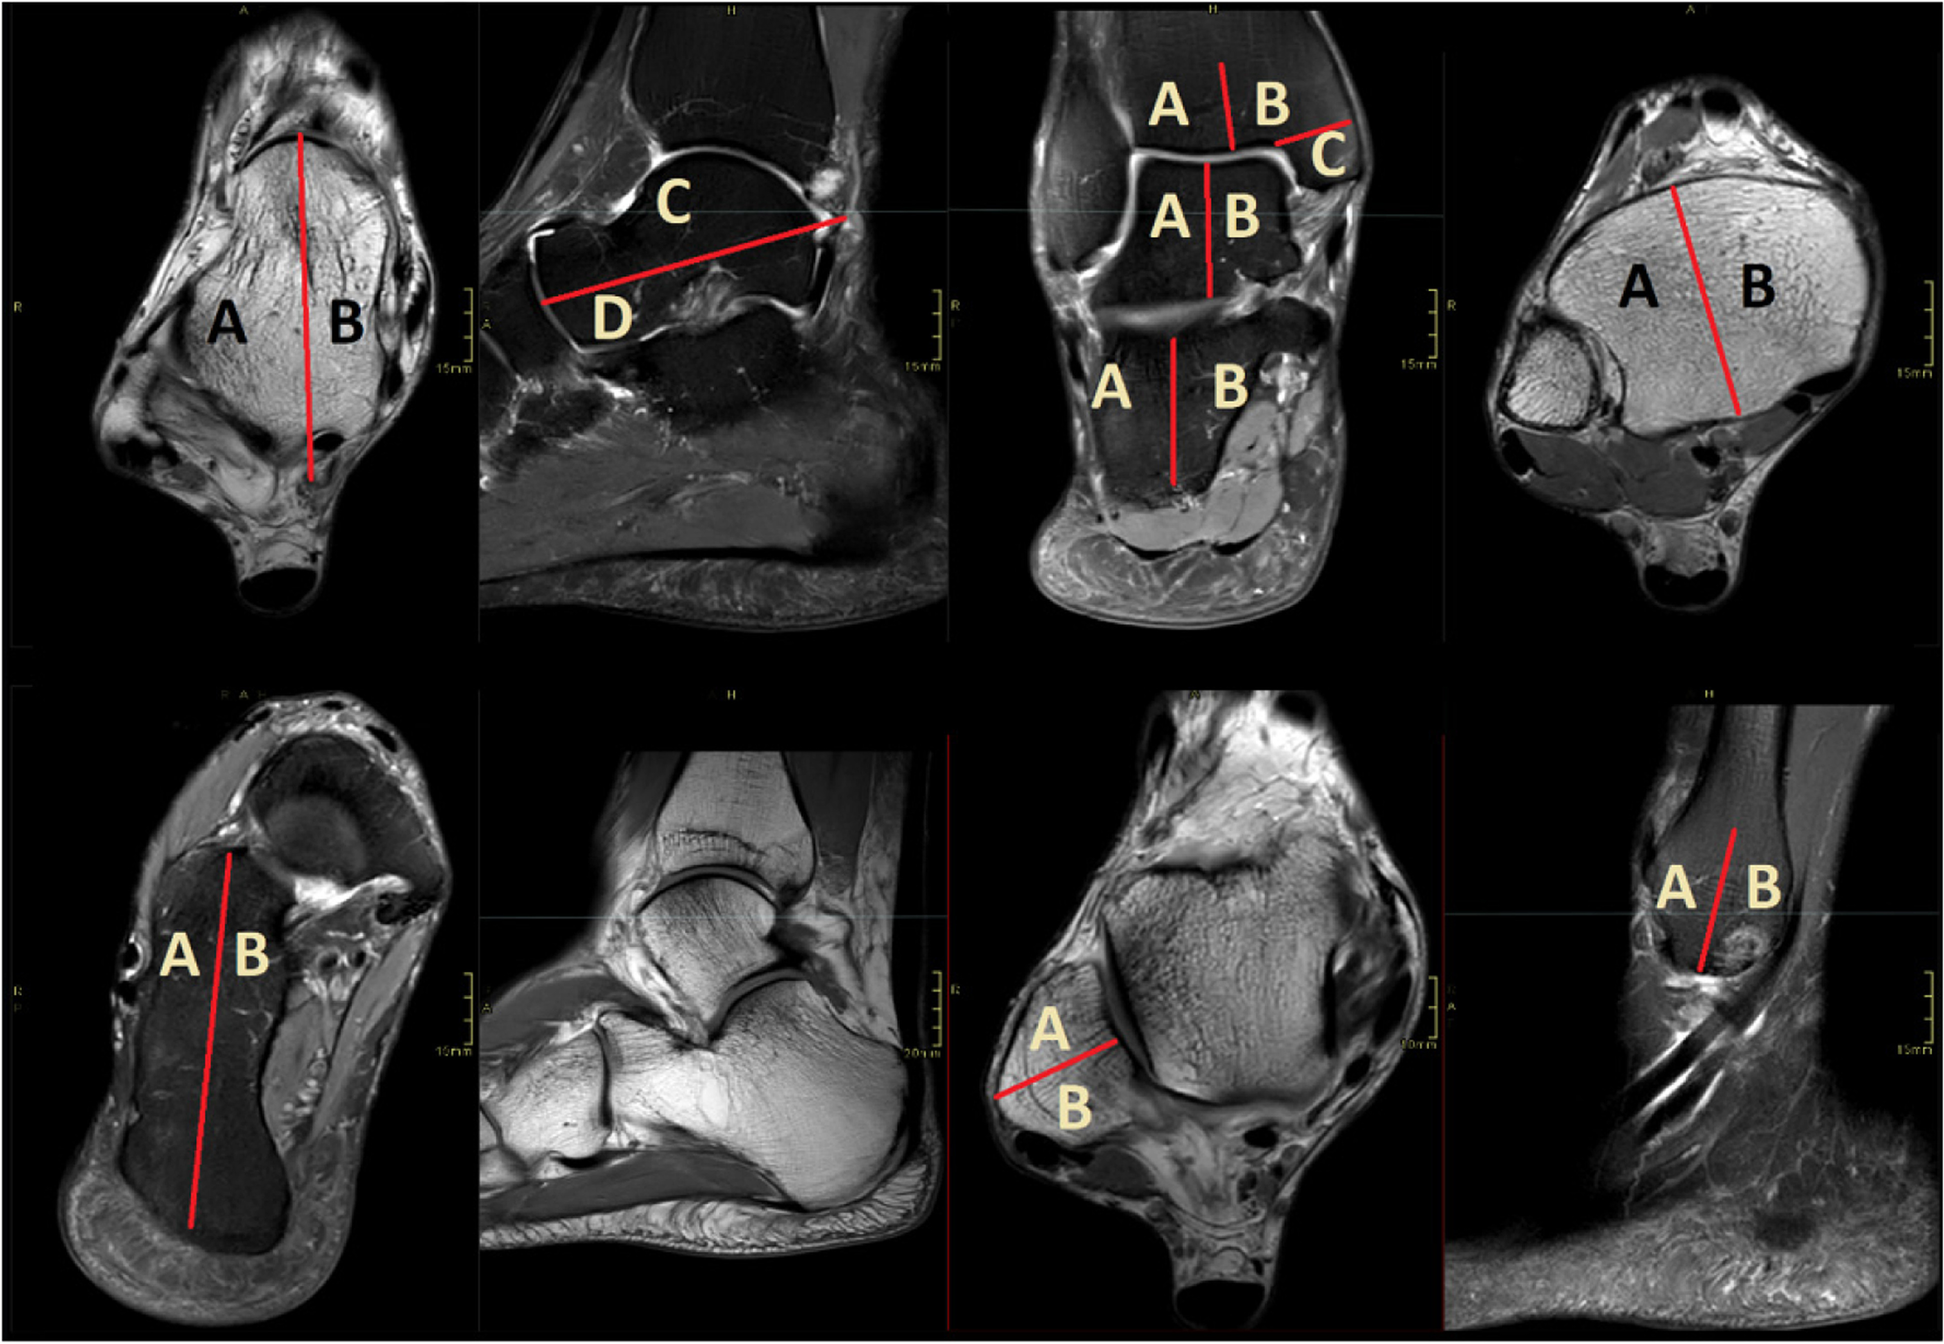

To more accurately evaluate localization of bone marrow edema, the tibia, lateral malleolus, talus and calcaneus were divided into sectors (see Fig. 2). The distal tibia was divided into three parts: the medial malleolus (Tibia C), the lateral half (Tibia A) and the medial half (Tibia B). The fibula was divided into an anterior half (Fibula A) and a posterior half (Fibula B). The talus was divided both in terms of superior (Talus C)/inferior (Talus D) and medial (Talus B)/lateral (Talus A). The calcaneus was divided into a lateral half (Calcaneus A) and medial half (Calcaneus B).

Fig. 2

Illustrating the defined distribution areas of bone marrow edema. Bone section coded as described in Sect. 2.6. A, D, G – proton density-weighted images; B, C, E, H – T2-weighted images with fat suppression; F – T2-weighted image